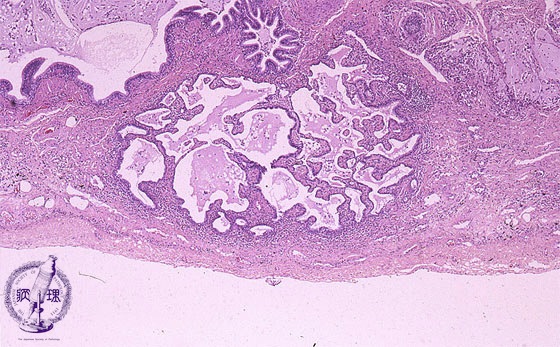

Microscopic views (HE stain, low power view): Honeycomb lesion.